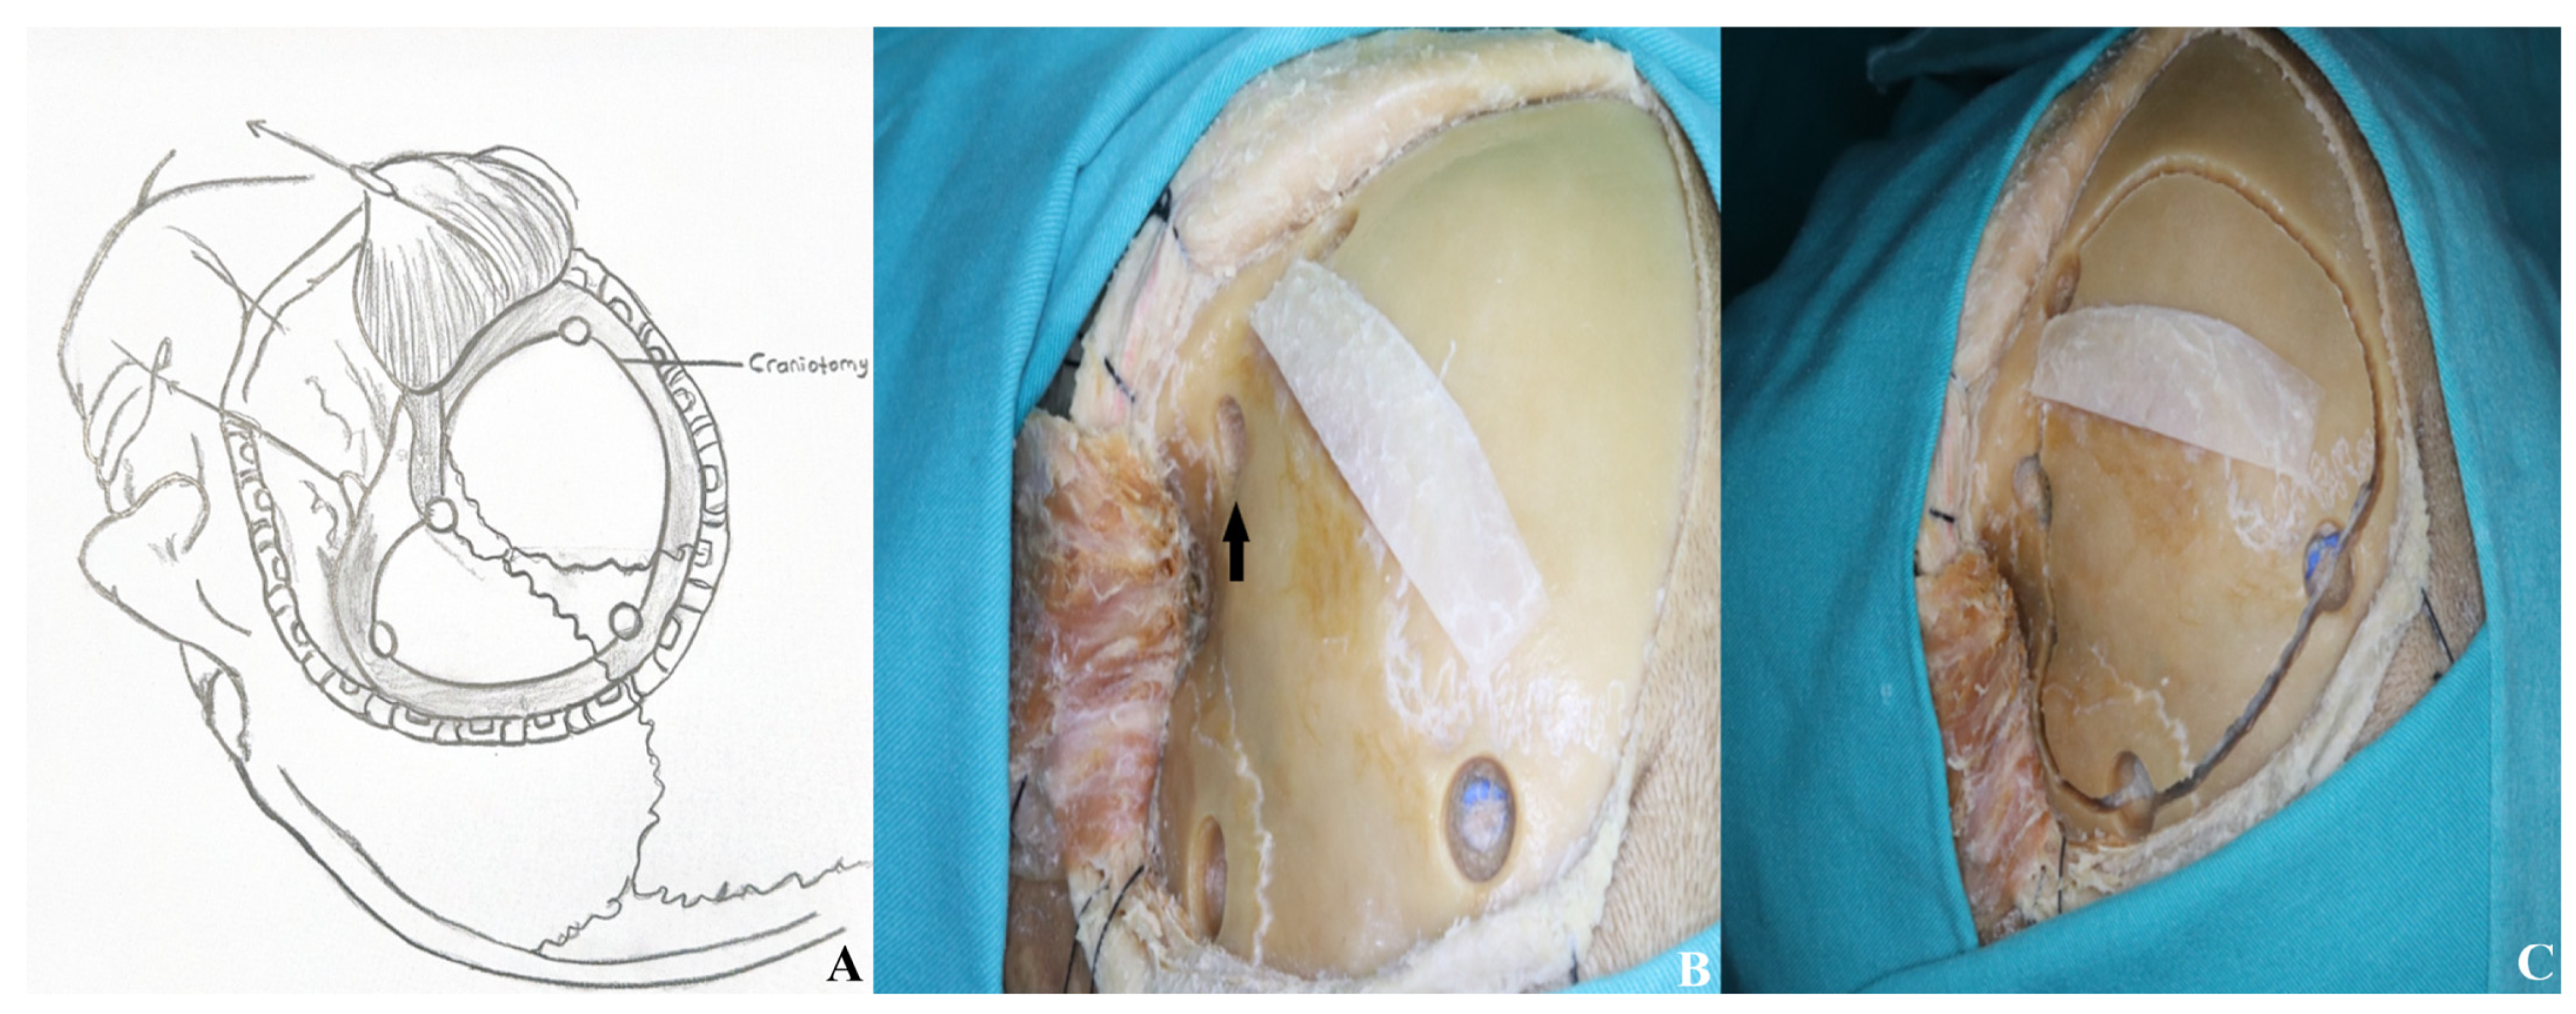

3.1.3. Craniotomy

3.1.4. Basal Drilling

3.1.5. Dura Incision